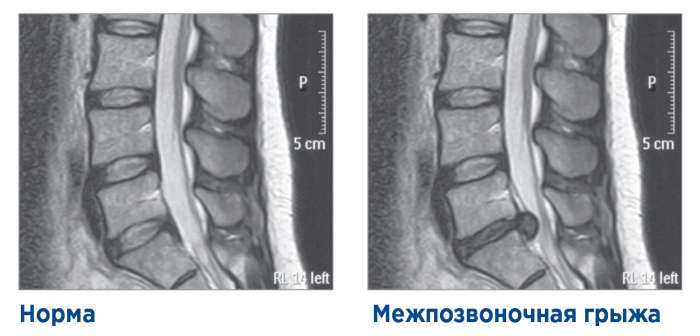

Чтобы понять, как появляется межпозвоночная грыжа, необходимо ознакомиться со строением позвоночника. Позвоночник является главной опорной структурой организма и состоит из цепи позвонков (33-34). Между позвонками находятся межпозвоночные диски, необходимые для гибкости и подвижности позвонков. Межпозвоночный диск в своём строении имеет ядро и фиброзное кольцо. Из-за чрезмерных физических нагрузок или травмы может произойти микротрещина в фиброзном кольце. В течение жизни трещина разрастается и приводит к выпячиванию ткани ядра за пределы позвоночника. Так начинает формироваться межпозвоночная грыжа.